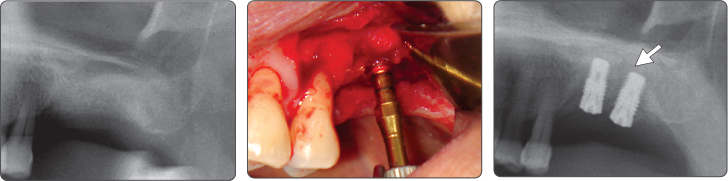

Последовательность манипуляций при синус-лифтинге

1. Синус-лифтинг (имплантат Ø4.0)

▶ Immediate Implantation and Sinus Lift Technique with Tap Drill (Ø4.0 Fixture)

2. Синус-лифтинг (имплантат Ø5.0)

▶ Immediate Implantation and Sinus Lift Technique with Tap Drill (Ø5.0 Fixture)